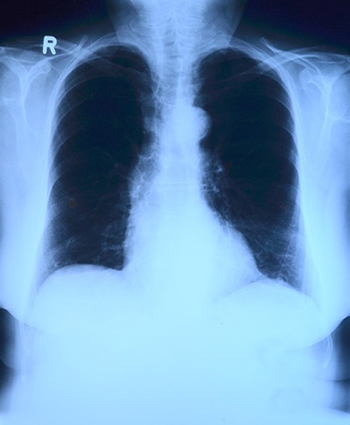

여성이 폐암 수술 후 생존율 높아

스웨덴 카롤린스카 연구소가 최근 폐암 수술 후 성별과 생존 사이의 연관성을 연구한 결과에 따르면 여성은 공존하는 건강 문제, 연령, 소득, 생활 방식, 수술 유형 및 정도, 종양 특성 및 종양 단계와 같은 요인과 관계없이 남성보다 폐암 수술 후 사망 할 확률이 27% 낮았다고 밝혔다. 폐암 치료 후 생존율의 성별 차이에 대한 이전 연구는 서로 상충되는 연구 결과가 많았다는 점에서 이번 연구결과는 주목되고 있다. 이번 연구를 주도한 Karolinska University Hospital의 심장흉부수술 전문의인 Erik Sachs 박사는 "이번 연구는 궁극적으로 환자의 결과에 영향을 미치는 체계적인 차이를 밝히는데 도움이 될 수 있을 것"이라고 말했다. 연구팀은 스웨덴에서 2008년부터 2017년까지 폐암 수술을 받은 6,500명 이상의 사람들에 대한 데이터를 분석했다. 환자의 절반 이상이 여성이었고, 평균 연령은 67세, 남성의 평균 연령은 68세였다. 여성은 흡연자일 가능성 및 공존하는 건강 문제가 적었다. 환자에 대한 후속 조치는 수술 후 1년, 5년 및 10년 후에 수행되었다. 조사결과 여성은 공존하는 건강 문제, 연령, 소득, 생활 방식, 수술 유형 및 정도, 종양 특성 및 종양 단계와 같은 요인과 관계없이 남성보다 폐암 수술 후 사망 할 확률이 27% 낮았다. 최근에 Chest 저널에 게재된 보고서에 따르면 여성과 남성의 차이가 그다지 크지 않은 어린이 환자를 제외한 모든 연령 그룹에서 여성의 사망 위험이 낮았다. 연구 공동 저자인 카롤린스카 연구소의 베로니카 잭슨(Veronica Jackson) 박사는 "이번 발견은 폐암의 예후가 개선될 수 있다는 것을 암시하기 때문에 중요하지만 이 분야에 대한 더 많은 연구가 필요하다. 구체적으로 생활양식, 사회 문화적 조건 및 치료 전달에 있어서 불평등의 존재를 조사하는 것이 가치가 있다."고 밝혔다. (HealthDay News) | |||||||||